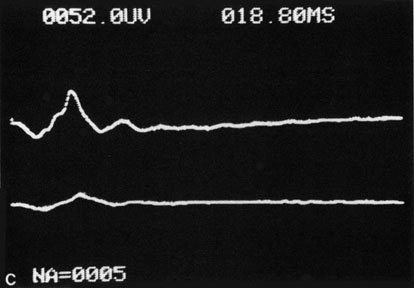

CENTRAL RETINAL ARTERY OBSTRUCTION Central retinal artery obstruction is one of the most sudden and dramatic events seen by ophthalmologists and was described as early as 1859.1 Although there have been numerous clinical and experimental studies of the pathophysiology of central retinal artery obstruction and although these studies have been augmented by the introduction of intravenous fluorescein angiography in the 1960s, the disease still has a relatively poor visual prognosis. The clinical picture is typically striking. Patients present with a sudden painless loss of vision. The appearance of a cherry-red spot in the fundus is characteristic (Fig. 1).2 The cherry-red spot appears because soon after obstruction of the blood flow to the inner retina, the normally transparent retina becomes opaque and blocks the brownish-red color from the underlying choroid, which is still supplied by blood. Because the retina overlying the foveola is relatively thin, however, the normal color of the choroid is still visible in this area.3,4 Although characteristic, the cherry-red spot is not pathognomonic for central retina artery obstruction.5 Sometimes the characteristic cherry-red spot does not develop; there may be only a slight accentuation of the brownish-red color in the foveola.4 It is not known how long it takes this cherry-red spot to appear, but in a primate model, it has appeared as early as 30 minutes after obstruction.6 An afferent pupil defect is usually present.2 With obstruction, virtually all eyes have narrowing and irregularity in the arteries and there is frequently an irregularity in the caliber of the retinal veins.2,4,6,7 Segmentation (boxcarring) of the blood column frequently develops; this segmentation is particularly noticeable in the veins and can be seen as a to-and-fro movement of the blood elements.3,4 Retinal hemorrhages, however, are not characteristic of central retinal artery obstruction.7 With time, the retinal opacity diminishes, generally leaving an optic nerve that is atrophic (Fig. 1). Frequently, thinned retinal arteries and veins also remain.7,8 No foveolar light reflex is evident, and a finely pigmented appearance of the macula is typical.7 In some cases, arterial collaterals develop at the optic disc.9–11 Rarely, anatomoses that exist between the central retinal artery and the ciliary arteries become visible as preretinal loops (Nettleship collaterals) after an occlusion at the edge of the disc.12,13,378In approximately 20% of patients, an embolus is evident somewhere in the arterial system.14 Emboli are discussed later. Intravenous fluorescein angiography is useful in showing the details of the abnormal circulation of a central retinal artery obstruction (Fig. 1). The principal abnormality is the delay in the appearance of the dye in the central retinal artery and its branches.2 Rather than the central retinal artery and its branches filling rapidly, considerable time may elapse before the entire arterial system is filled.15 The filling of the retinal arteries is often abnormal, with the fluorescein partially filling an artery (a dye front) or hugging the vessel wall, as in normal venous filling.15 Segmentation of the blood column is often well defined on fluorescein angiography.15 Venous filling is usually slowed and occasionally the dye does not progress beyond laminar flow during the study.14 In approximately 10% of eyes that have central retinal artery obstruction, there are abnormal choroidal filling defects, reflecting posterior circulation obstruction. These defects can occur even in patients who appear to have a typical central retinal artery obstruction.14 Leakage of dye from the vessel walls is not normally seen except at the site where an embolus lodges within a retinal artery.16 With time, the flow within the artery and its branches is reestablished and the appearance of the intravenous fluorescein angiogram may return to normal. The electroretinogram (ERG) is usually abnormal in central retinal artery obstruction. The b-wave is reduced, indicating a marked abnormality in the circulation of the inner retina.17,18 The a-wave, indicating normal photoreceptor function, is preserved or accentuated. There does not appear to be a good correlation, however, between the extent of b-wave abnormality and the degree of retinal function,3 although Yotsukura and Adachi-Usami420 reported that the b-wave amplitude increased with visual improvement. The photopic negative response (PhNR) shows severe depression in this condition reflecting the significant loss of the ganglion cells and their axons.377 The electrooculogram may be either normal or abnormal. Visual field defects are usually profound but either occasionally a small portion of the temporal peripheral visual field remains or the patient has a large central scotoma.3 The onset of obstruction occurs most often between the hours of midnight and 6 AM, with the second most common period being between 6 AM and noon.2 Most patients with central retinal artery obstruction complain of a sudden loss of visual acuity in the affected eye; most of these patients present with visual acuity ranging from finger-counting to light perception.14 Only about 5% of patients have visual acuity of no light perception and most of these have involvement of the posterior ciliary circulation, which can be seen on either intravenous fluorescein angiography or electrophysiology.14 Without a partial central retinal artery obstruction or a spared cilioretinal artery (to be discussed), it is unlikely that any patient will have initial visual acuity better than finger-counting.14 With or without treatment, most eyes retain visual acuity of finger-counting to light perception. Patients with a spared cilioretinal artery do not seem to have a follow-up visual acuity that is significantly different from those without a spared cilioretinal artery.14 Central retinal artery obstruction is caused by the disruption or cessation of blood flow to the central retinal artery, its branches, and the retinal layers supplied by those vessels. The inner two thirds of the retina derives its blood supply from the central retinal artery and its branches; the outer third of the retina is supplied from the choroidal circulation.19–21 The central retinal artery and its branches function as an end artery, and with the exception of a few anastomotic connections between the retina and the ciliary circulation at the optic disc, there are no other anastomoses.19 No intrinsic retinal vessels are present in the fovea because the inner retinal layers are not present in this area.19 Histopathologically, when a central retinal artery obstruction occurs, the retina initially becomes edematous. With time, all the retinal layers supplied by the central retinal artery and the artery's branches, including the nerve fiber layer, ganglion cells, inner plexiform layers, and the inner portion of the inner nuclear layer, are lost.20 In trypsin digest preparations after obstruction of the central retinal artery, the greatest change is in the capillary bed,22 where extensive ischemic changes take place. Usually, little attempt is made to repair the retina with gliosis or neovascularization.20 The most common site of obstruction of the central retinal artery is at the level of the lamina cribrosa.20 Clinically, it is possible to examine the blood flow velocity in the central retinal artery in a noninvasive manner, using a variety of techniques.21 The most useful appears to be color Doppler imaging, providing simultaneous Doppler and B-scan ultrasound images of the optic nerve head, which primarily represents flow in the central retinal artery.23 Studies using this technique demonstrate a marked reduction of or no blood flow in the central retinal artery with an acute central retinal artery occlusion that returns to normal with time.24 Characteristics of the retinal blood flow can be measured clinically with retinal Doppler velocimetry.385 This is an instrument that can measure the blood column diameter, the centerline blood velocity, and the blood flow in major retinal vessels. However, when evaluating the blood flow in the optic nerve, choroidal, and retina, the Doppler laser flowmetry is more sensitive to the blood flow in the superficial layers than in the deeper layers.410 Masaoka and colleagues384 studied the hemodynamic changes in the retinal circulation with a scanning laser ophthalmoscope and intravenous fluorescein angiography. This technique allows the assessment of erythrocyte velocities and movement with high resolution continuous images and is a useful technique for the evaluation of hemodynamic changes in vascular occlusions. Analysis of the retinal nerve fiber layer by one of the confocal laser scanning tomography techniques can provide information about a central retinal artery occlusion. Foroozan and co-workers383 studied patients with a central retinal artery occlusion within 1 week of occlusion with a scanning laser polarimeter. Diffuse attenuation of the retardation of the nerve fiber layer surrounding the optic nerve was seen in all eyes studied. Four patients were scanned in follow-up at intervals ranging from 1 week to 6 weeks; all had unchanged studies.383 Optic coherence tomography (OCT) of an acute central retinal artery occlusion shows a slight increase in the thickening of the retina and reflectivity of the inner layers of the retina that correspond to the opacity seen clinically (Fig. 1).409 With time, the disc becomes atrophic and the retina thinner. Experimental studies of central retinal artery obstruction in the cat25 and the rhesus monkey26–28 have increased our understanding of arterial obstruction. The most clinically relevant finding is that there is a period in which a total lack of blood flow (ischemia) to the inner retina can be tolerated; that is, if the blood flow is not obstructed longer than this period, visual function may return to normal. This critical time in the cat eye is 90 minutes,25 and in the young, healthy rhesus monkey it is 100 minutes26–28—any longer than this and the histologic changes are irreversible and the animal has permanent visual loss. Hayreh and co-workers379,380 have repeated this experiment to determine how long the retina can survive central retinal artery occlusion in middle-aged and elderly rhesus monkeys, a situation that might be more applicable to the human situation where most occlusions occur in older patients. That study showed that an occlusion of less than approximately 100 minutes produced no permanent damage and that an occlusion of longer than 240 minutes produced massive and irreversible retinal damage. It is not known why the older monkeys had a longer retinal survival time with occlusion of the central retinal artery than younger monkeys. Because there is no evidence that the monkey and the human have different retinas,379 the studies by Hayreh and co-workers have implications for studies that attempt to treat central retinal artery occlusion. Any treatment of this condition will almost certainly have to be initiated within 100 to 240 minutes, assuming the occlusion is total, or the patient will likely have permanent damage to the retina, regardless of treatment. On average, central retinal artery obstruction occurs in patients who are in the fifth or sixth decades of life, with the age range varying from 17 to 84 years. Fewer than 10% of patients are younger than 30 years of age.14,29,30 In some cases, the cause of central retinal artery obstruction is relatively clear, such as when due to a visible embolus. In other cases, however, especially when found in association with a systemic disorder such as diabetes, the association is less clear. Table 1 lists some of the conditions associated with central retinal artery occlusion. Arteriosclerosis is probably the most commonly associated systemic condition. With the progressive buildup of subendothelial atheromatous material, the lumen of the central retinal artery becomes narrowed over time and eventually may become occluded.20 This association is inferred because most patients with central retinal artery obstruction are in the fifth to sixth decades of life, when atherosclerotic changes are expected. TABLE 1. Conditions Associated With Retinal Arterial Obstructions